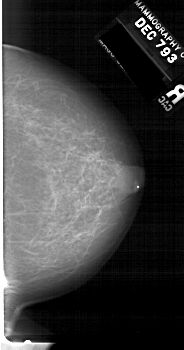

A_1513_1.LEFT_MLO

LEFT_MLO LINES 6496 PIXELS_PER_LINE 3496 BITS_PER_PIXEL 12 RESOLUTION 43.5 OVERLAY